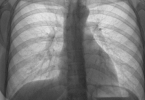

听诊时双肺底部可闻及类似Velcro撕开音的细湿啰音,是肺泡壁增厚和微小气道塌陷的特征性表现。该体征在疾病早期即可出现。

运动时呼吸困难呈进行性加重,初期仅在爬楼或快走时出现,后期静息状态下也会发生。这与肺泡-毛细血管单位受损导致氧气弥散障碍直接相关。